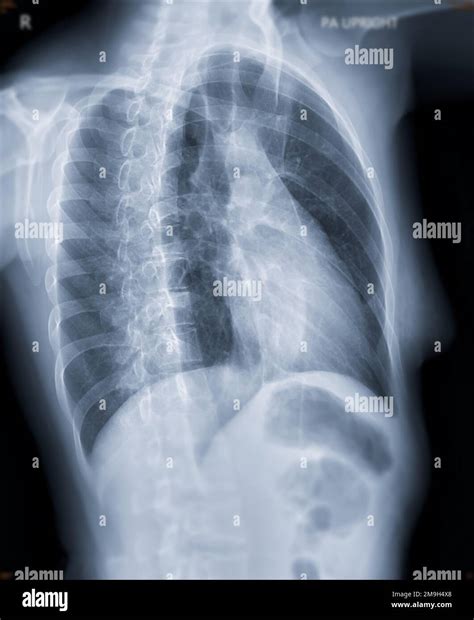

The Right Anterior Oblique view is an imaging technique used in cardiac angiography and other diagnostic procedures. It involves positioning the patient and the imaging equipment at a specific angle to capture a clear view of the heart from the right side and slightly from the front. This angle allows for a detailed examination of the right ventricle, the right atrium, and the pulmonary arteries.

• Detailed Visualization of the Right Ventricle: The RAO view provides a clear image of the right ventricle, which is often obscured in other views. This is crucial for diagnosing conditions such as right ventricular hypertrophy and pulmonary hypertension.

• Assessment of Pulmonary Arteries: The view allows for a detailed examination of the pulmonary arteries, helping to identify blockages or abnormalities that could indicate pulmonary embolism or other vascular issues.

• Evaluation of Cardiac Valves: The RAO view can also provide insights into the function and structure of the tricuspid and pulmonary valves, aiding in the diagnosis of valvular diseases.